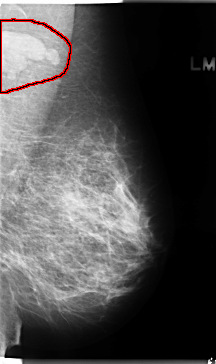

C_0136_1.LEFT_MLO

LEFT_MLO LINES 4728 PIXELS_PER_LINE 2808 BITS_PER_PIXEL 12 RESOLUTION 50 OVERLAY

FILE: C_0136_1.LEFT_MLO.OVERLAY

TOTAL_ABNORMALITIES 1

ABNORMALITY 1

LESION_TYPE MASS SHAPE LOBULATED MARGINS CIRCUMSCRIBED

ASSESSMENT 5

SUBTLETY 5

PATHOLOGY MALIGNANT

TOTAL_OUTLINES 1

BOUNDARY